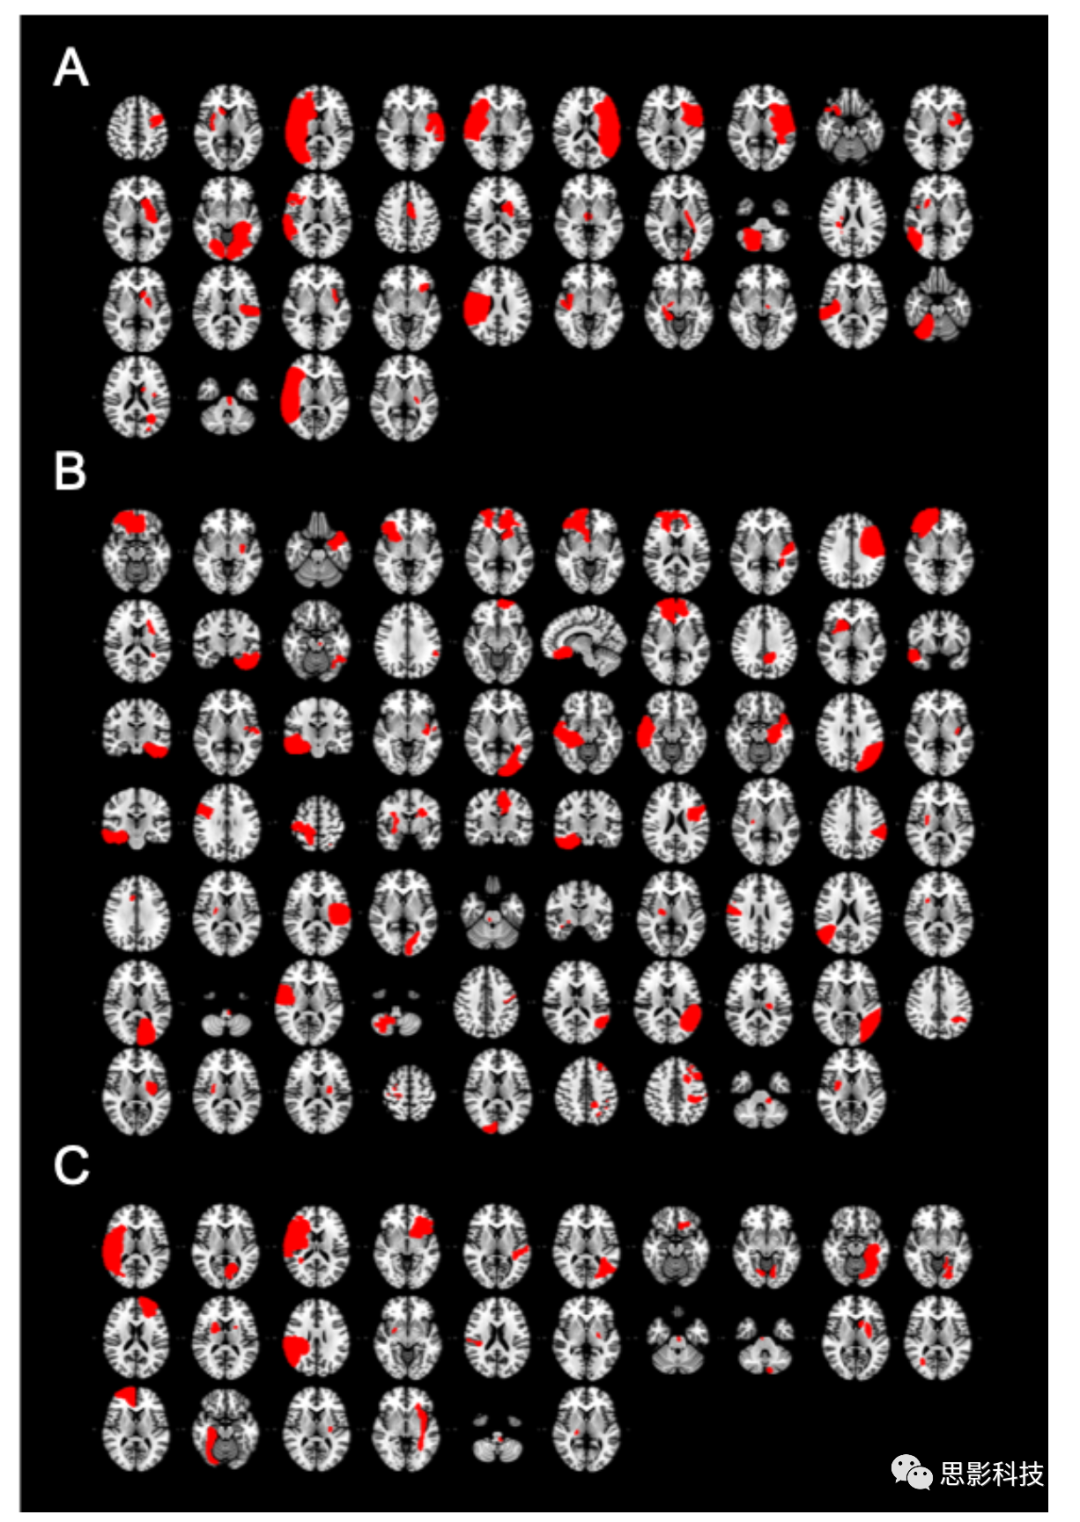

S1:吸煙者隊列病變。導致吸煙成癮緩解的病變(A,n = 34)。未戒煙患者的病變(B,n = 69)。戒煙但未緩解的患者的病變(Cn = 26)。每個切片代表不同的患者。組間的病變大小沒有差異(單因素方差分析,F = 1.78p = 0.17)。